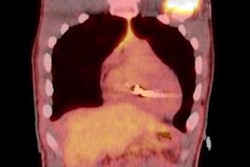

A handful of studies with small patient cohorts have evaluated PET/MRI in this regard. A December 2015 study by Hanneman et al found that when paired with MRI, PET achieved positive results for cardiac sarcoidosis for all eight patients (100%), compared with only four patients (50%) with PET/CT.

More recently, a January 2019 study of 10 patients by Wisenberg et al concluded that PET/MRI provided diagnostic-quality FDG images that were "at least equal to or better than those obtained with either the PET/CT scan, and subjectively crisper MR images" than those from a 1.5-tesla MRI scanner (J Nucl Cardiol, January 2, 2019).